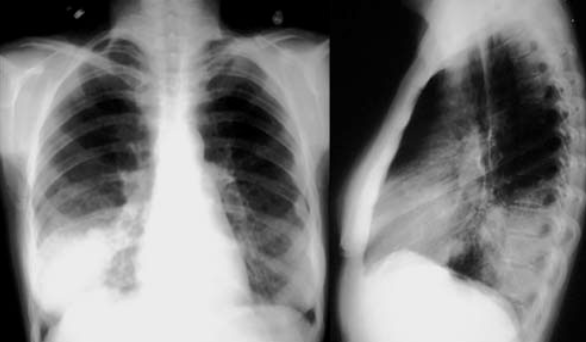

- CXR:

- The appearance of consolidation on CXR is reliable for the diagnosis of pneumonia, but CXR appearances are not reliable for distinguishing between viral and bacterial infection as there is considerable overlap.

- The CXR may appear normal early in the disease. However, as an approximate guide:

- Viral pneumonia:

- Patchy perihilar infiltration, hyperinflation, atelectasis

- Bacterial pneumonia:

- Lobar consolidation (air bronchogram) occasionally with parapneumonic effusion. Pneumatocoele and abscesses suggest staphylococcal pneumonia

Chest X-Ray showing patch of pneumonia

Image of chest x-ray displaying the interstitial pattern seen in viral pneumonia. The interstitial pattern shows fine lines radiating from the hila.

These chest X rays compare clear, healthy lungs with the cloudy, inflamed lung tissue of pneumonia.

Right lower lobe consolidation in a patient with bacterial pneumonia.